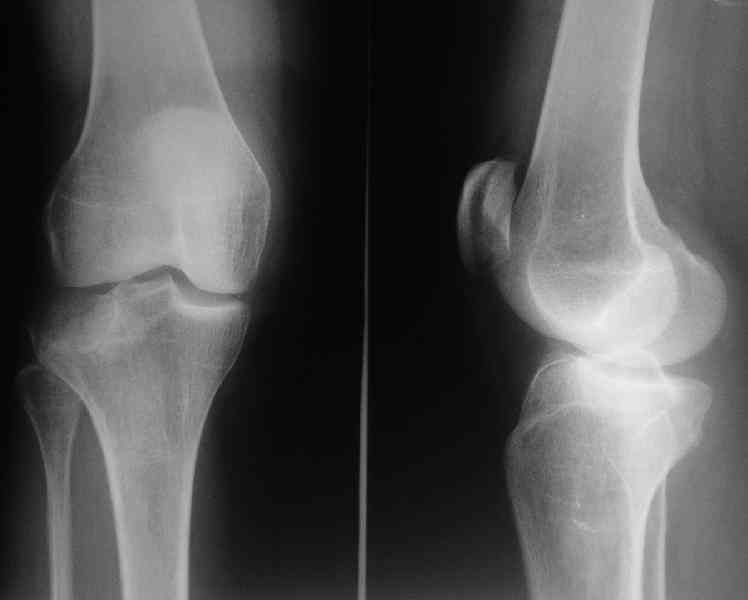

Здравствуйте, уважаемые коллеги!Подскажите, пожалуйста, какой выбрать доступ и способ фиксации при импрессионном переломе заднего отдела наружного мыщелка большеберцовой кости. Женщина 40 лет, травму получила 02.01.2008, катаясь на горных лыжах.Есть ли здесь необходимость использовать задний доступ, или можно справиться через наружный? Есть ли шансы сделать закрыто - под ЭОП через медиальное "окошко" поднять забойником суставную поврехность? Какой лучше использовать фиксатор?Спасибо.